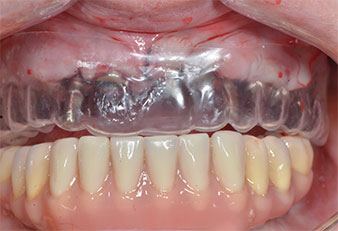

Tre anni dopo era il momento di una protesi dentaria mascellare dello stesso tipo. In base alla pianificazione con CBCT, il rialzo del seno mascellare è stato evitato con l'ausilio di impianti corti e una dima chirurgica è stata utilizzata per trasferire le posizioni pianificate alla cresta alveolare (Figg. 1 e 2).

A causa dell'osso relativamente duro (D2) in quest'area, le sedi dell'impianto di 10 mm nelle posizioni 11 e 21 sono state finalizzate con un trapano rotante da 4 mm di diametro, in combinazione con un contrangolo chirurgico W&H WS-75 L, il motore per impianto W&H Implantmed e il modulo opzionale Osstell ISQ di W&H. Al contrario, a causa dell'osso morbido, le sedi posteriori sono state preparate a un diametro finale di 3 mm utilizzando lo strumento Piezomed I3P. Gli impianti sono stati infine posti per via transgengivale sull'osteointegrato per tre mesi (Figg. 6-10). La protesi dentaria esistente è stata mantenuta su quattro impianti provvisori (Fig. 8).